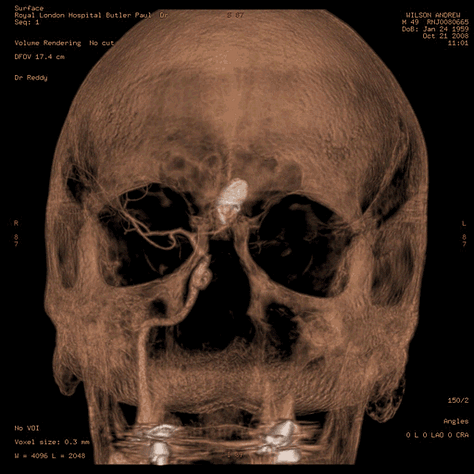

A PET scan is organised a few days later, at St Barts Hospital, in the shadow of St Paul’s. The body is flooded with a tracer radioactive fluid, after which you are locked into a lead-lined box for three-quarters of an hour to allow it to bake in. The scanner then detects where the tracer has been absorbed by cell growth anywhere in the body it is directed, producing reams of flowing light captured to film, copies of which—scans of my own body—are used throughout this post.

The moment I saw the very first scan the doctors showed me (bottom right, above: an MRI, rather than PET, as it happens)—on a small monitor wheeled into my cubicle at the Homerton—seemed to say everything at once. As I turned my head to look at the image of my brain on the monitor, I glimpsed also the tattoo on my left arm suddenly aligned with it (bottom left)—a tattoo of a bhikkhu meditating in flames, inked twenty years earlier, with the bhikkhu meditating as descibed in the Buddha’s Adittapariyaya Sutta (Fire Sermon)—such that the tattoo of the bhikkhu and the scan of the brain, aligned properly. One presaged the other by years, holding out its hand to the other. They reflected each other so neatly, with the tumour in the cerebellum showing up as the red-orange fire bursting through from within, which the bhikkhu sits through.

On being rushed to the Royal London for an operation to seal the aneurysm with platinum coils, it seems that the moment the equipment entered my brain (inserted by way of the veins in the leg, with a camera threading the coils, winding its way through your heart before landing at the center of the brain to do its job: a “GDC coiling of anterior communicating artery aneurysm”), my brain simply shut down in a vasospasm, cutting off the blood to the brain. The operation was stopped immediately, and I was returned to the Intensive Care Unit, where my family was told to expect my death at any moment, or, short of that, for me to emerge as paraplegic.